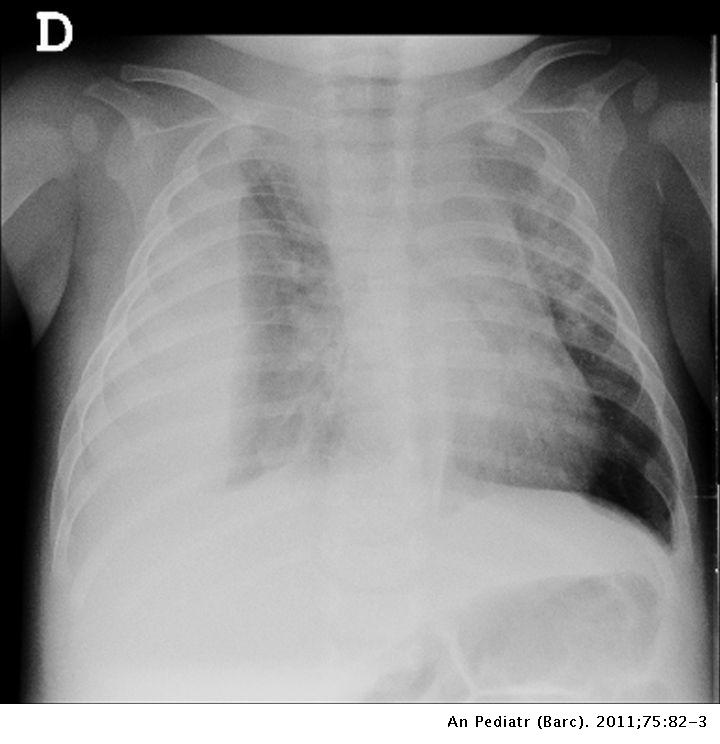

- Radiografía de tórax: Una radiografía de tórax puede mostrar líquido en el espacio pleural.

Neumonía y derrame pleural por Staphylococcus aureus sensible a meticilina productor de leucocidina de Panton-Valentine: muy infrecuente y muy peligroso | Anales de Pediatría